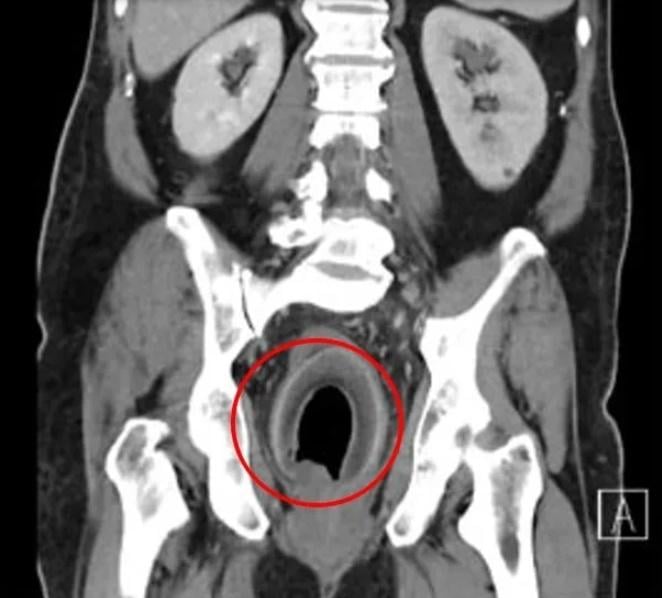

綜合報道,高雄義大醫院一般醫學外科主任、大腸直腸科主治醫生陳致一坦言,這是第一次碰到塞椰子的個案。他表示,男子是獨自求診,聲稱前一晚塞了東西入肛門裡,膀胱很漲,未能排尿,經電腦掃描(CT)發現,男子的膀胱漲到有如一個橄欖球,估計裡面大概有近2,000毫升的尿,幾漲爆,另外直腸也有個圓形異物,向男子查詢後,對方回答:「椰子」。醫護試過先為男子導尿,但被椰子卡住,尿管插不入膀胱,再試過用手及多種器械,伸進去男子肛門,但無論怎麼夾、怎麼挖,椰子仍是原封不動。經過評估,倘若繼續拖延下去,恐會膀胱爆破、直腸壞死,陳致一立即進行手術,以類似「剖腹產」的方式,剖開直腸取出椰子。但到底如何將椰子塞入肛門,男子直至出院仍不願透露。

陳致一指,肛門塞異物最可能的危險,就是造成肛門撕裂傷,恐留下括約肌鬆弛、滲便的後遺症,再者異物也可能傷害直腸組織,可能被塞傷、塞破,而上述男子所塞的椰子,更是卡住膀胱出口,還有膀胱漲破的風險,奉勸有此習慣者,還是不要「逆其道而行」,以免後悔莫及。網上圖片顯示,那個取出的椰子的長度有約10厘米。